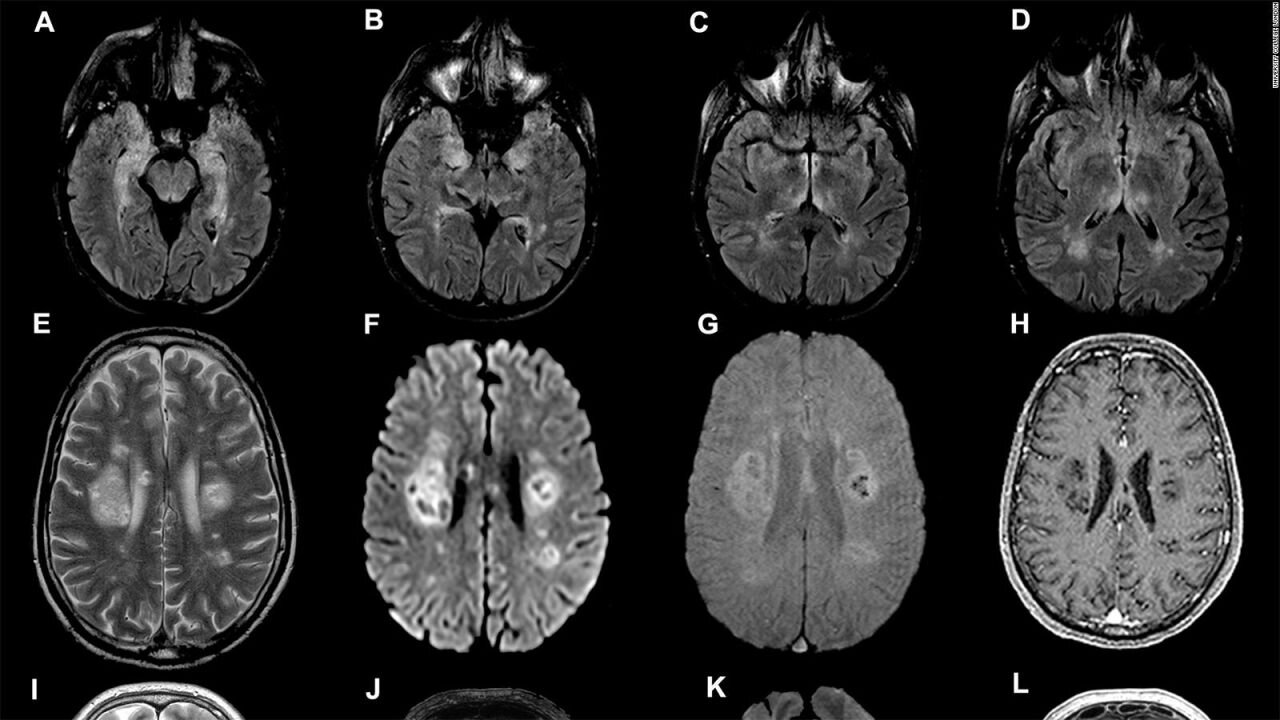

El trabajo analizó casi 4.000 escáneres cerebrales de personas entre 1 y 90 años, trazando por primera vez un mapa detallado de cómo evoluciona el cableado neuronal a lo largo de la vida. Los investigadores concluyeron que el cerebro no progresa de forma lineal, sino que experimenta puntos de inflexión estructurales que modifican su funcionamiento.

Los científicos describen un primer período que va desde el nacimiento hasta los 9 años, marcado por la consolidación de redes neuronales y la eliminación de sinapsis poco utilizadas.

Luego, el cerebro entra en una fase adolescente que se extiende hasta los 32 años, caracterizada por un aumento sostenido de la eficiencia en las conexiones y un refinamiento de la materia blanca.

El tercer gran hito ocurre justamente en esa edad. Cerca de los 32 años, el cerebro adopta una configuración considerada plenamente adulta, fase que se prolonga por más de tres décadas. Según los investigadores, esta etapa coincide con una mayor estabilidad en rasgos como la personalidad y la inteligencia.

Posteriormente, alrededor de los 66 años, aparece una etapa de envejecimiento temprano, marcada por una disminución progresiva en la conectividad. Finalmente, hacia los 83 años, se inicia la fase de envejecimiento tardío, donde estos cambios se intensifican.